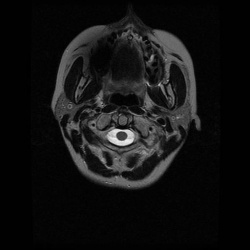

в 1995 г субтотально удалена параганглиома левого кавернозного синуса